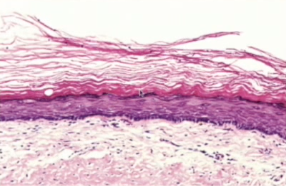

OKC’s have what kind of tissue

parakeratinized

orthokeratinized epithelium